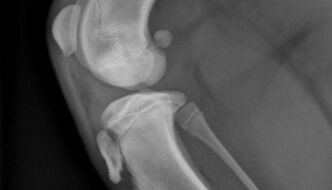

9 month old male Rhodesian Ridgeback

Today's case is a 9-month-old male Rhodesian Ridgeback who has been lame on the left pelvic limb for three weeks. Take a look and post your interpretation. … [Read more...]